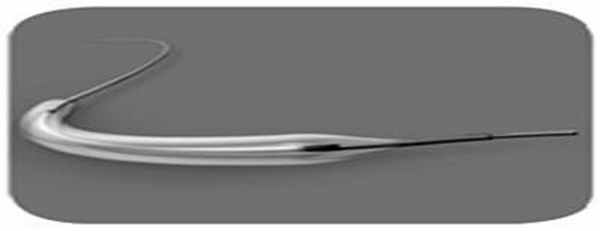

В 30 нед беременности нами совместно с сосудистым хирургом под постоянным ультразвуковым контролем проведена внутриутробная вальвулопластика овального окна. Через правое предсердие введен проводник в полость левого предсердия, а затем стандартный коронарный дилатационный баллонный катетер MINI TREK 2,0 × 12 мм (рис. 3).

Рис. 3. Баллонный катетер MINI TREK 2,0 × 12 мм.